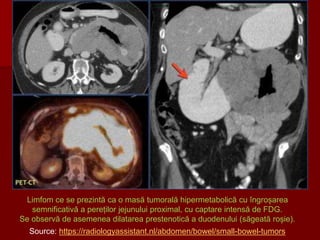

Limfom ce se prezintă ca o masă tumorală hipermetabolică cu îngroșarea

semnificativă a pereților jejunului proximal, cu captare intensă de FDG.

Se observă de asemenea dilatarea prestenotică a duodenului (săgeată roșie).

Source: https://radiologyassistant.nl/abdomen/bowel/small-bowel-tumors